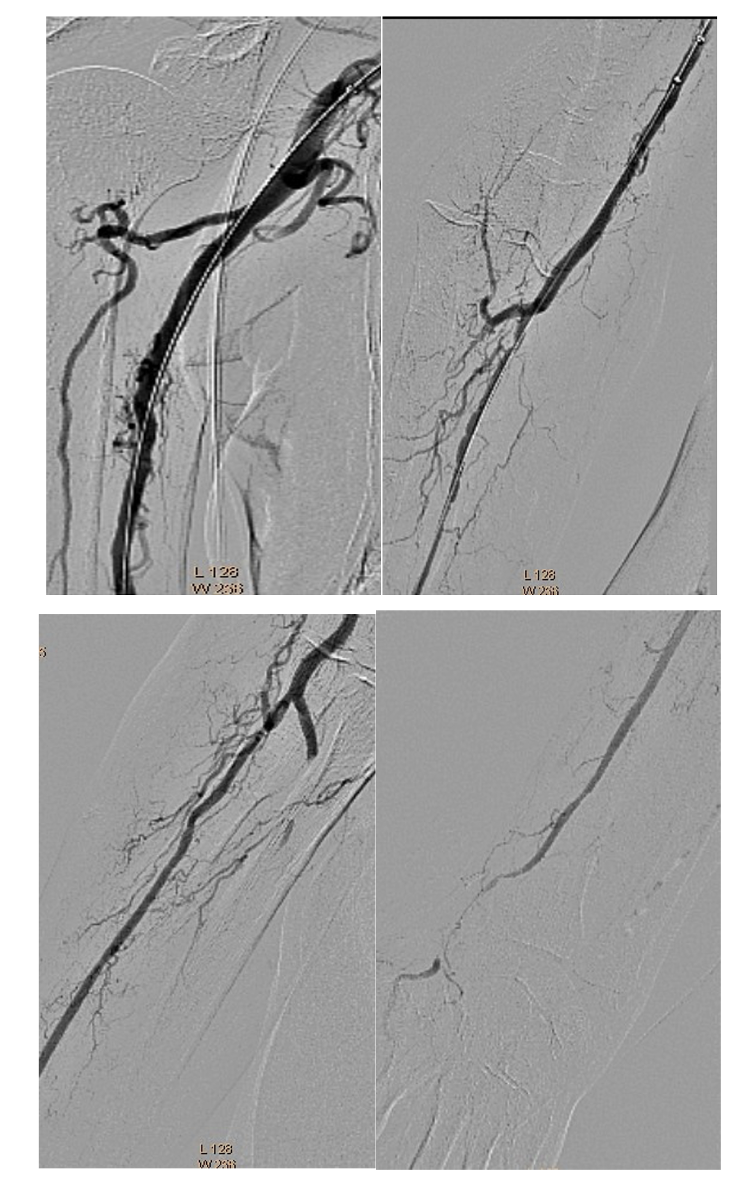

A 6 Fr/90 cm Fortress introducer sheath (Biotronik) was placed at the right subclavian artery (Figure 3). Recanalization was done with a 0.018" Glidewire Advantage (Terumo) and a Trail Blazer Angled Support Catheter (Medtronic) (Figure 4). Balloon dilatations were done with a 2/120 mm Passeo-18 (Biotronik) and a 3/120 mm Passeo-18, without effect (Figure 5). Then, a 0.014" Fielder wire (Asahi) was placed to the palmar arch. Thromboaspiration of red thrombotic masses was done with a 6 Fr Eliminate aspiration catheter (Terumo). Again, there was no distal flow.

A 0.035" Storq wire (Cordis) was then placed in the right radial artery. Effective EVT with a 2.06 mm AngioJet Solent Omni was performed, first in the right brachial artery, then in the axillary artery (Figure 6). The brachial artery was successfully recanalized, but distal embolization in the brachial artery bifurcation occurred again. We repeated EVT with the same 2.06 mm AngioJet Solent Omni in the brachial and radial arteries. Blood flow was restored in the right brachial and radial arteries (Figure 7).

The same introducer was redirected with the tip in the right common femoral artery. PTA of the right SFA, PFA, and popliteal and posterior tibial arteries was performed. Recanalization with a 0.035" Stiff Glidewire (Terumo) and a NaviCross Support Catheter (Terumo). The “riding” thrombus at the SFA/PFA bifurcation then migrated distally and occluded the SFA and PFA (Figure 8). We began EVT from the proximal segment of the SFA, with the same 2.06 mm AngioJet Solent Omni catheter. EVT was performed in the middle segment of the SFA and the popliteal artery (Figure 9). Due to residual thrombosis in the distal segment of the SFA, a balloon dilatation with a 5/120 mm Armada catheter (Abbott) was done (Figure 10).

Thereafter, the right PFA was recanalized with a 0.035" Angulated Glidewire (Terumo) and again EVT was performed with the 2.06 mm AngioJet Solent Omni (Figure 11).

Balloon dilatations in the posterior tibial and tibiofibular trunk were done with 2/120 mm and 3/120 mm Pacific Plus balloons (Medtronic). Because of persistent thrombosis in the proximal segment of the posterior tibial artery, EVT was again performed with the 2.06 mm AngioJet Solent Omni. Finally, distal blood flow was restored in the right SFA, PFA, and popliteal and posterior tibial arteries (Figure 12).